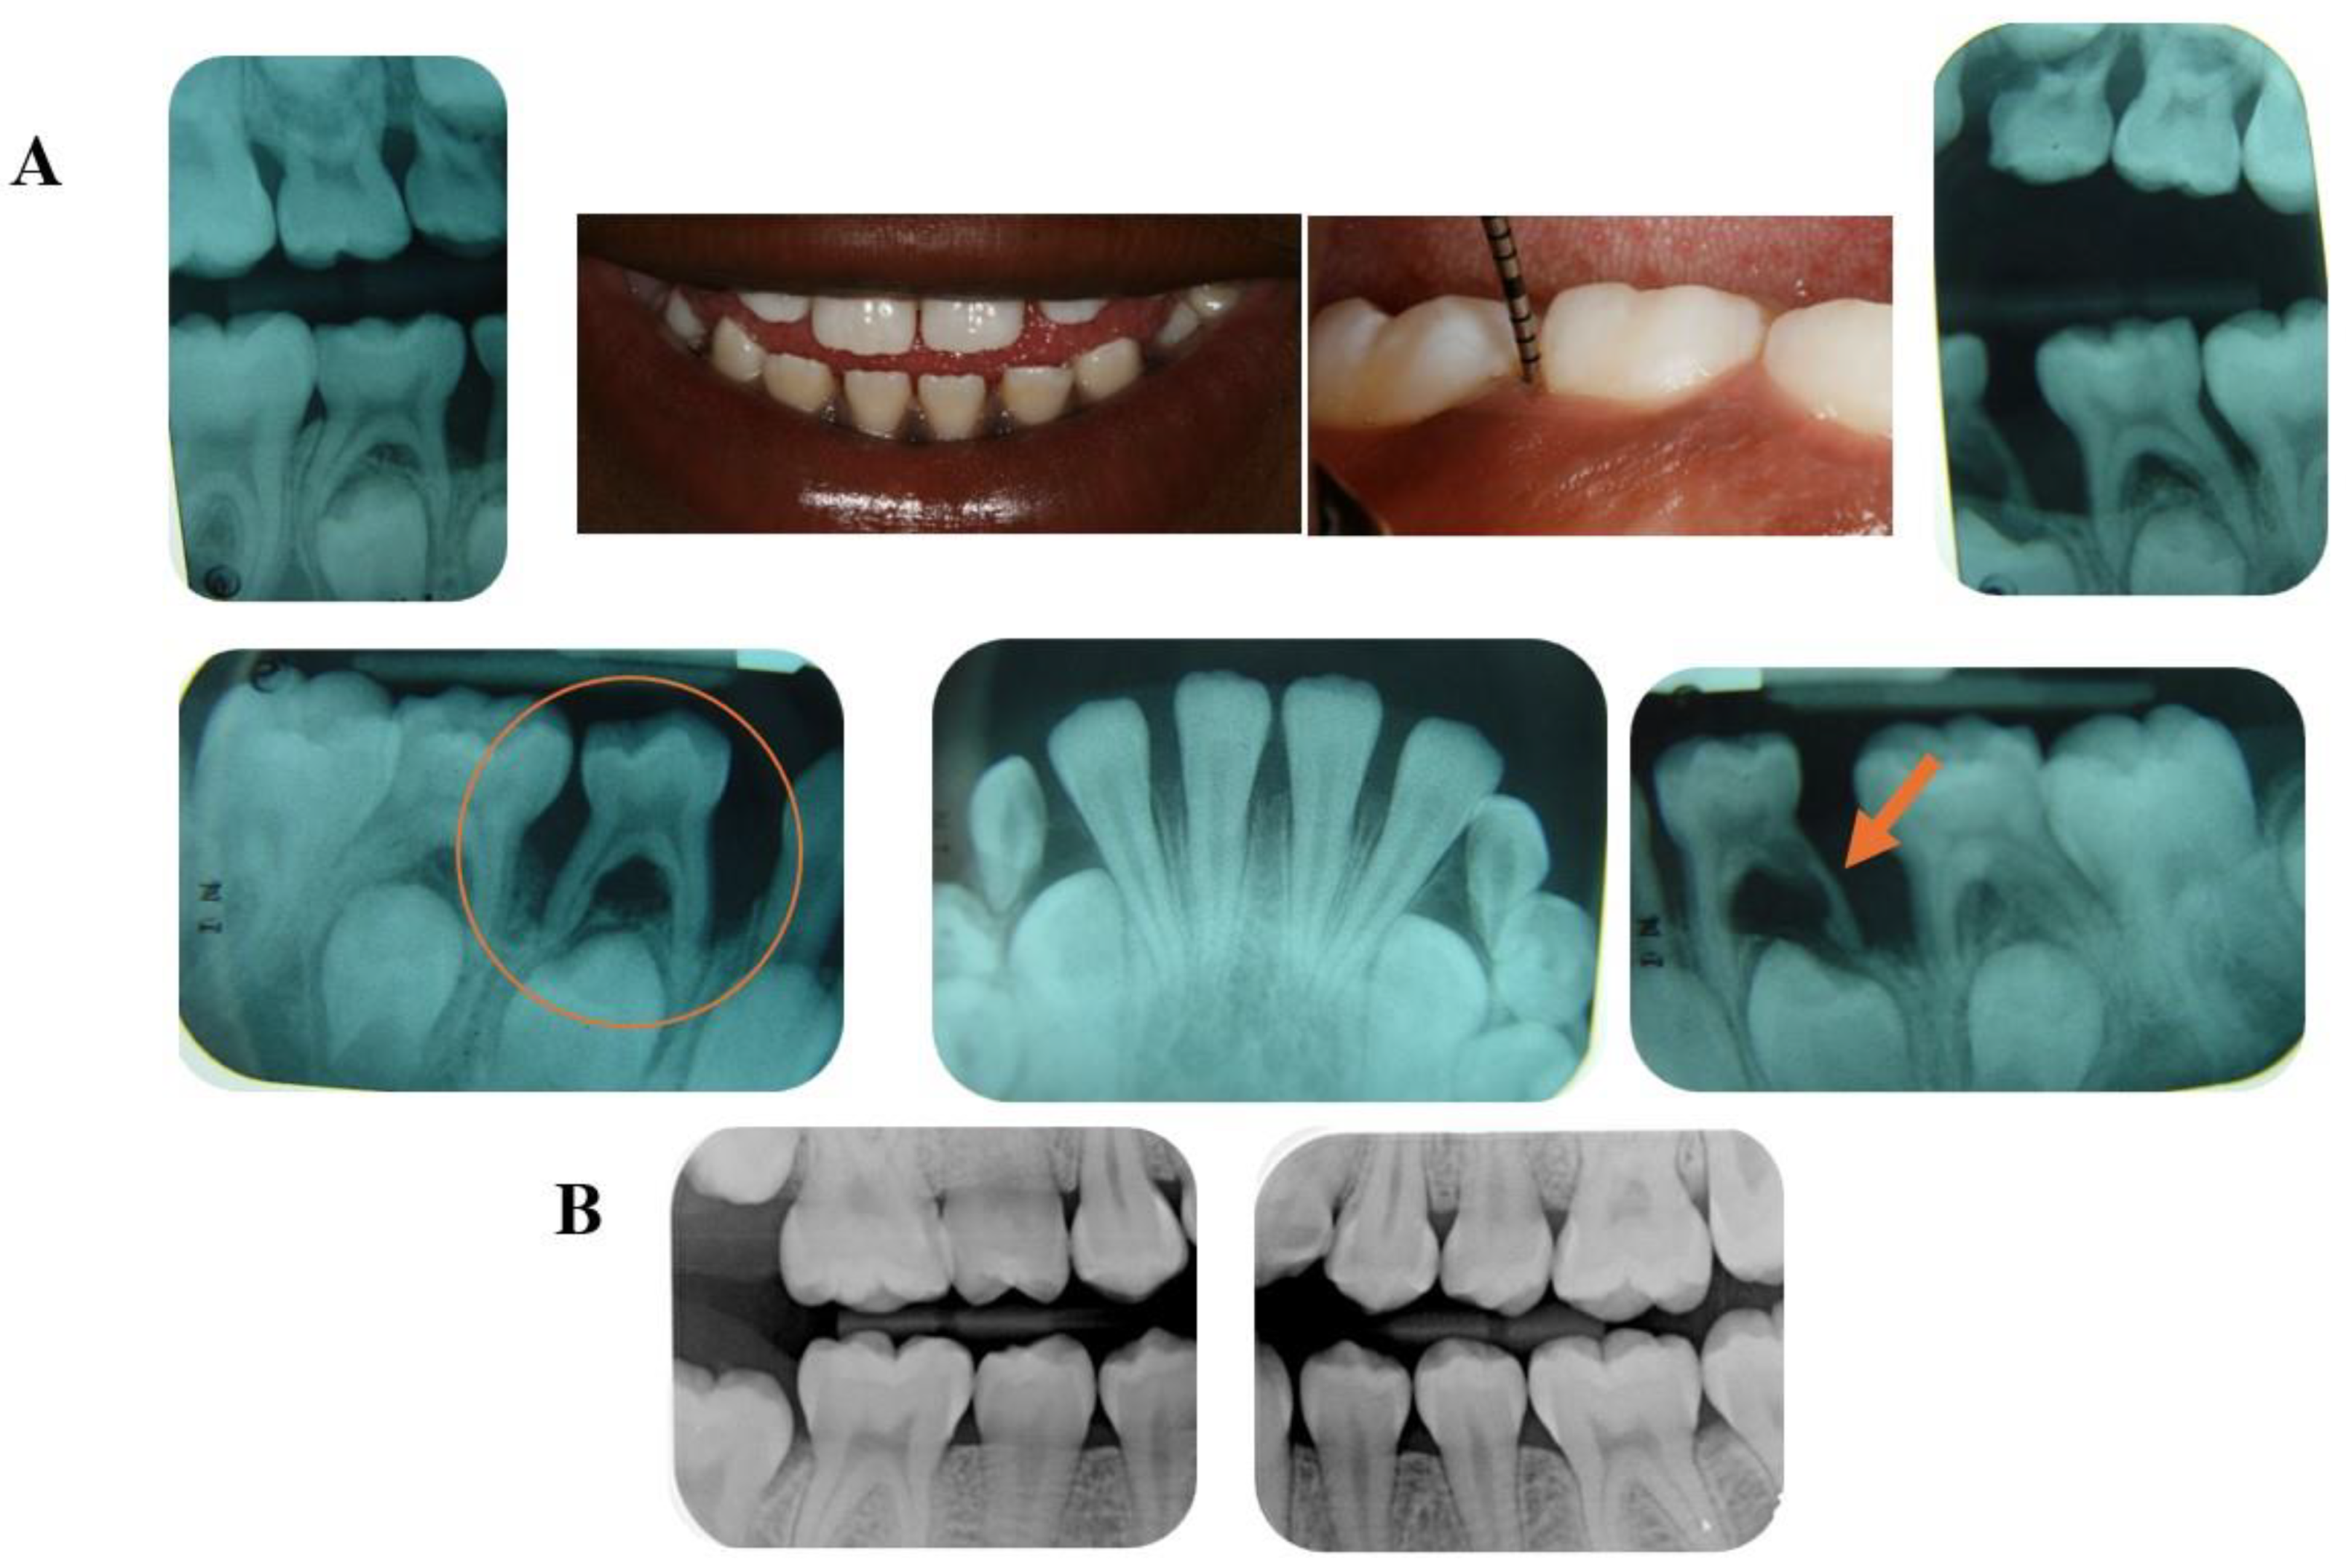

Figure 1.

Clinical Case: 8-year-old African American female diagnosed with C-MIP in primary dentition. Patient smiles with low gingival margin inflammation; however, probing depth > 5 mm in the first molar. In the X-ray, severe bone loss in the lower first primary molars (orange arrow and circle) along with internal and external resorption of the lower left primary first molar in the primary dentition (orange arrow) (A). Permanent dentition in healthy conditions following therapy (SRP+ABX) in the primary dentition (B). (Source of the image [10]).